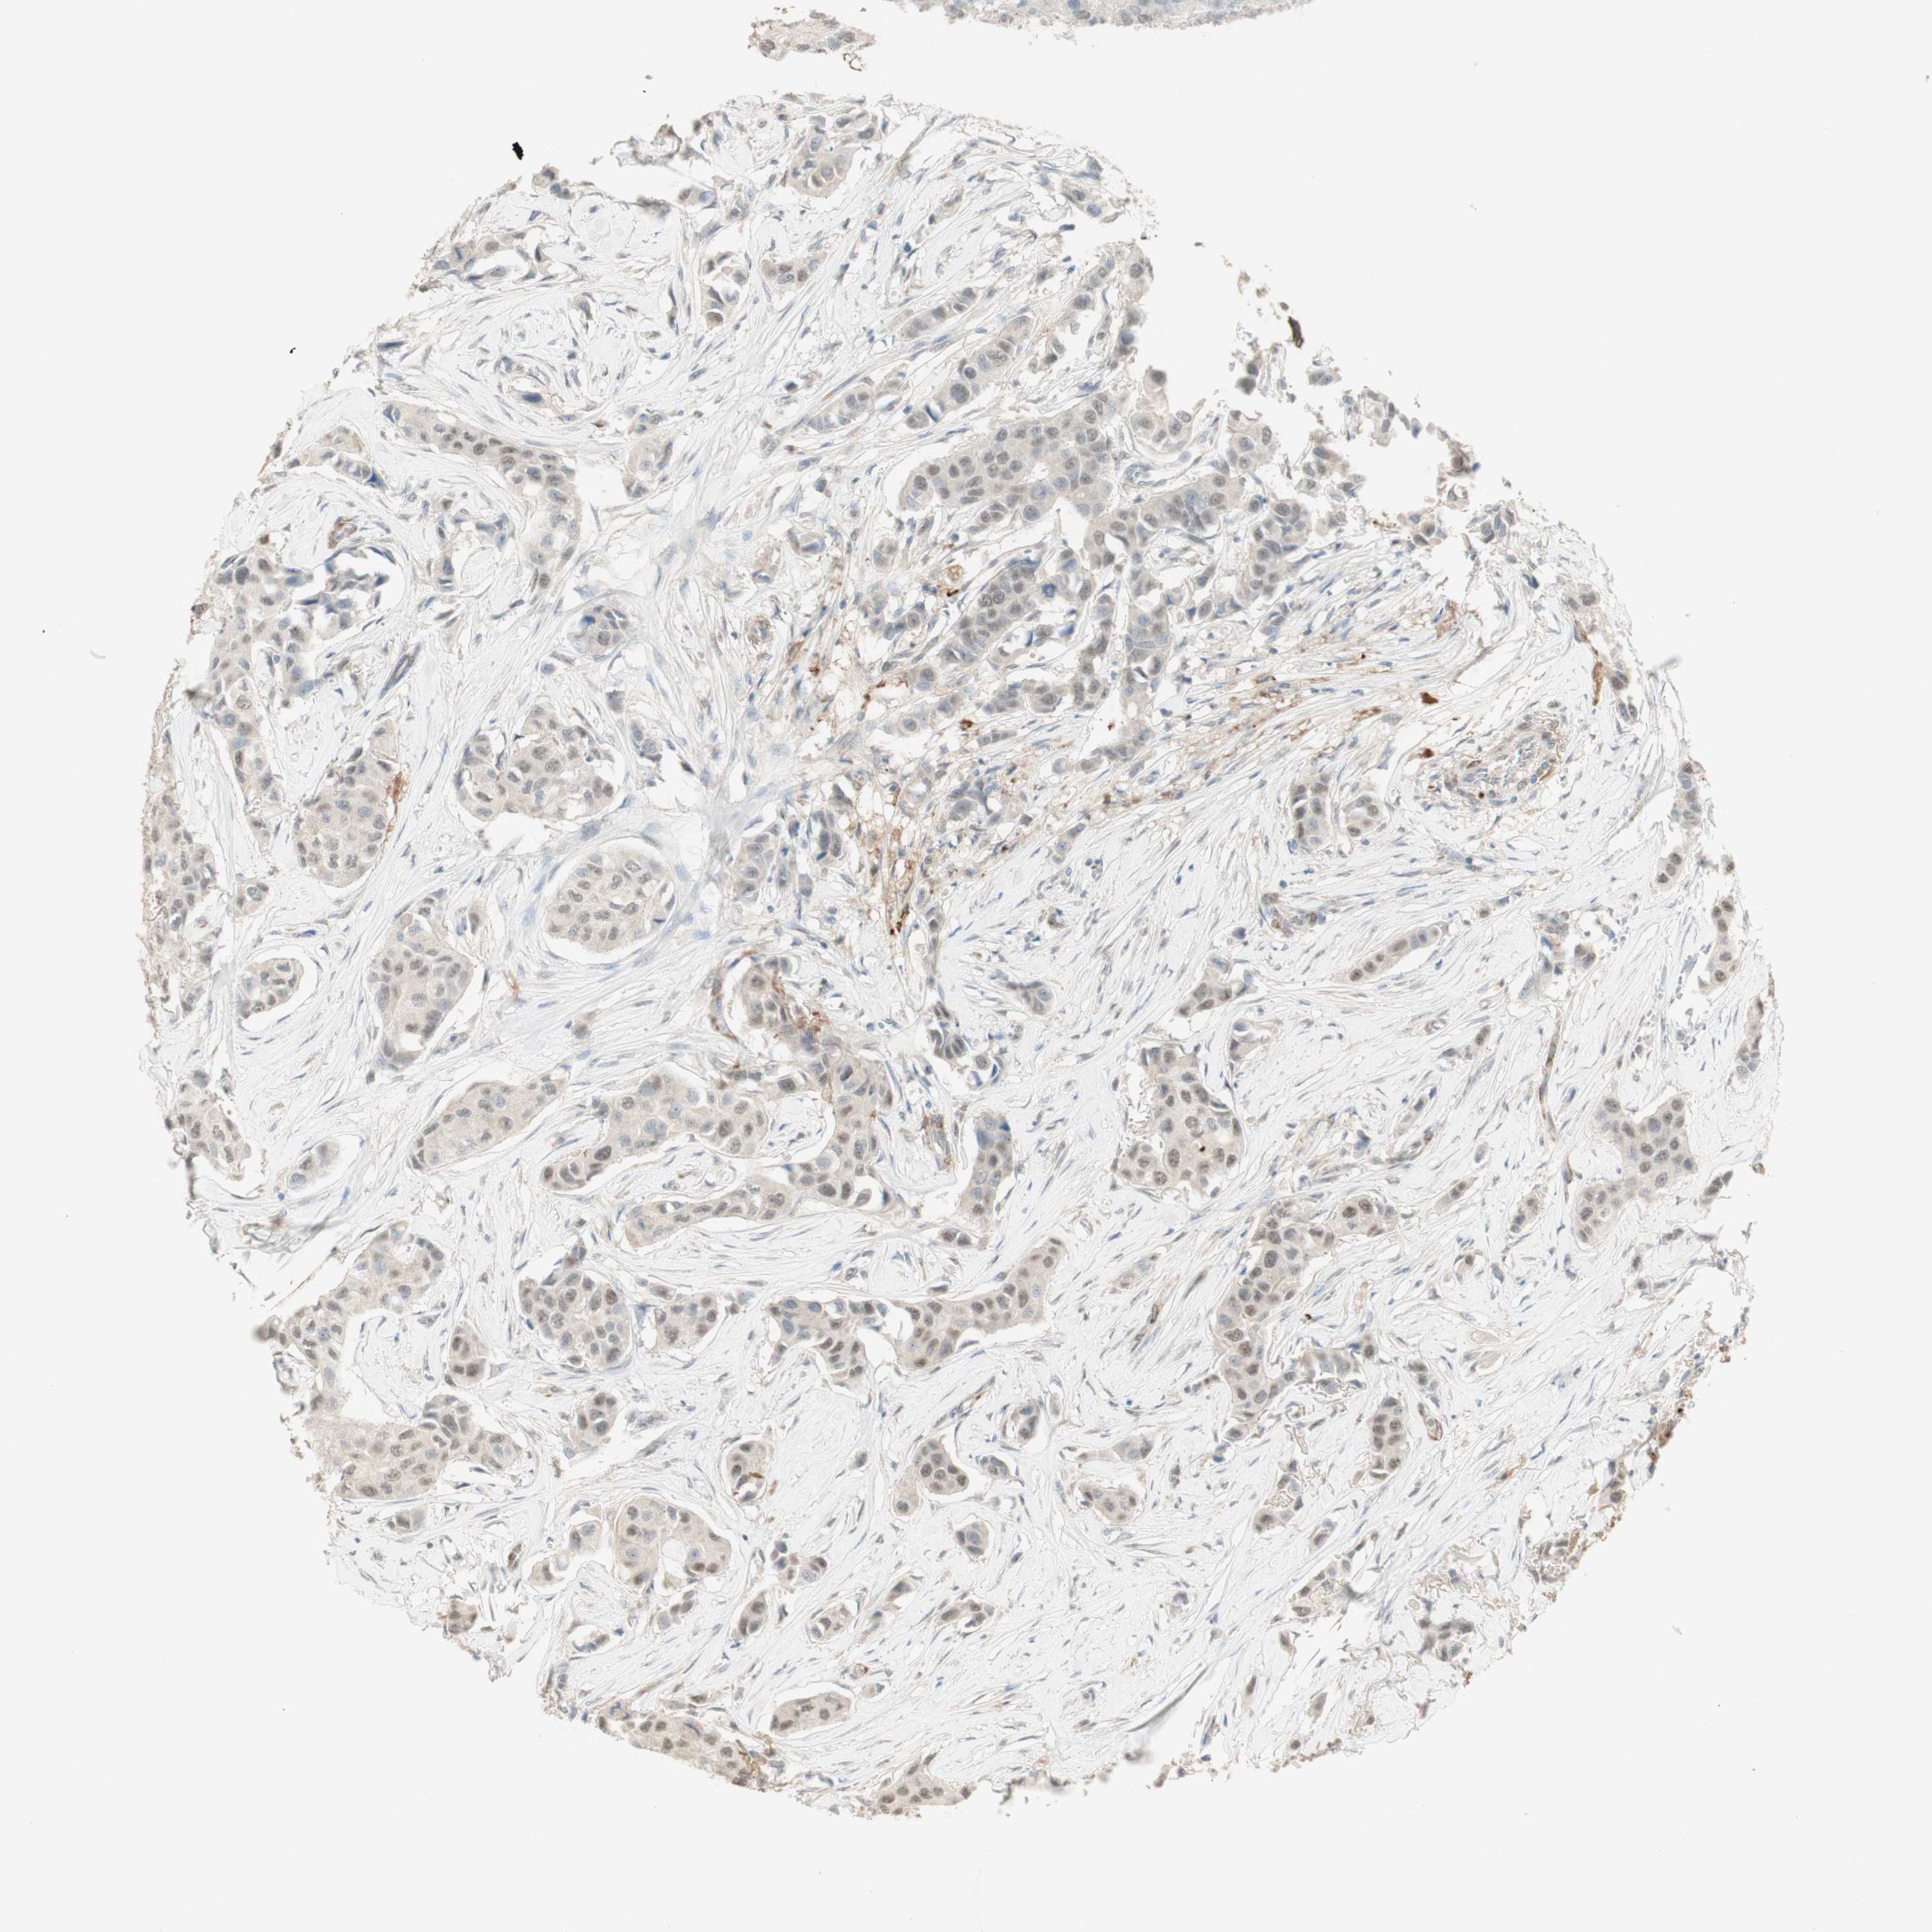

BRCA TCGA BRCA VALIDATION PROTEIN EXPRESSION

ANTIBODIES

AND

VALIDATION